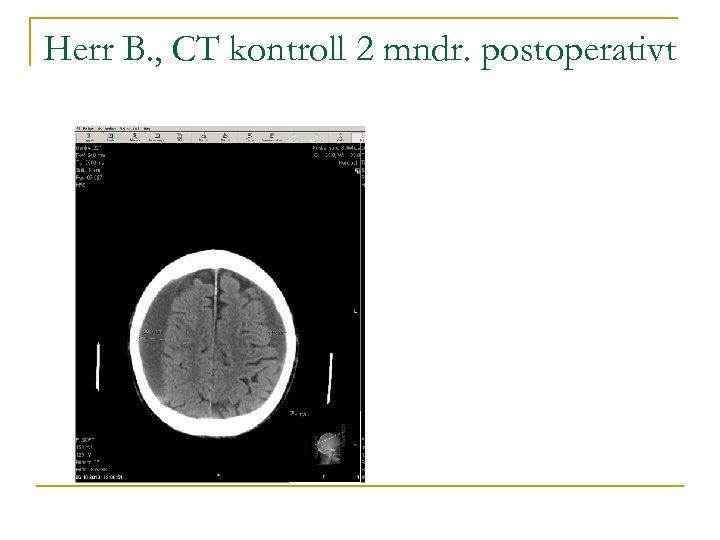

Herr B. blir operert to dager senere. n n Evakuerer hematom bilat. Dren høyre side, fjernes 1. postopr. dag. Overflyttes lokalsykehuset. Gradvis bedring. Utskrevet til hjemmet med daglig hj. spl. Kontroll to mndr. senere. Sønnen mener han er i sin habitualtilstand. MMS 17/30 p.

Herr B. , CT kontroll 2 mndr. postoperativt